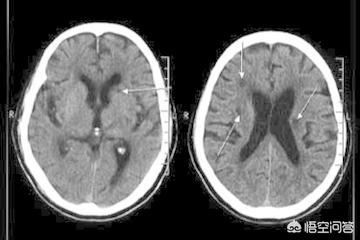

- しかし、臨床像の違いに加えて、時に臨床症状だけでは診断はできないまた、以下のような画像検査も行う。頭蓋CTと頭蓋MR.ラクナ梗塞にせよ脳梗塞にせよ、脳組織が虚血・低酸素状態にあるだけで、梗塞脳組織の液状化壊死はないため、24時間以内の頭部CTでは大きな変化はない。24時間以内であればある程度判別可能である。症状の急性期には、臨床では頭蓋MRが検査の第一選択となる。 MRIには様々なシーケンスがあり、症例によって異なるMRIシーケンスを用いて適切な検査を行うことができる。脳梗塞の診断において、DWIシーケンスは状況を明らかにするのに非常に直感的である。。

(3)検査:頭部のCT検査または核磁気検査。核磁気検査が最もよく、脳の対応する部分に空洞病巣を見つけることができる。

脳梁性脳梗塞は無症状の人もおり、頭蓋骨のCTやMRI検査で発見されることが多い:

片麻痺、顔面神経麻痺、失語症、半盲症が60%、言語障害、嚥下障害、顔面神経麻痺、上肢の軽度の脱力が20%;

片麻痺が10%。

しかし、ほとんどの人は目立った後遺症はない。

脳出血と脳梗塞は症状が同じであり、症状から判断することはできないので、脳梗塞とラクナ脳梗塞の診断は、脳CTや脳MRIでさらにはっきりさせる必要がある。